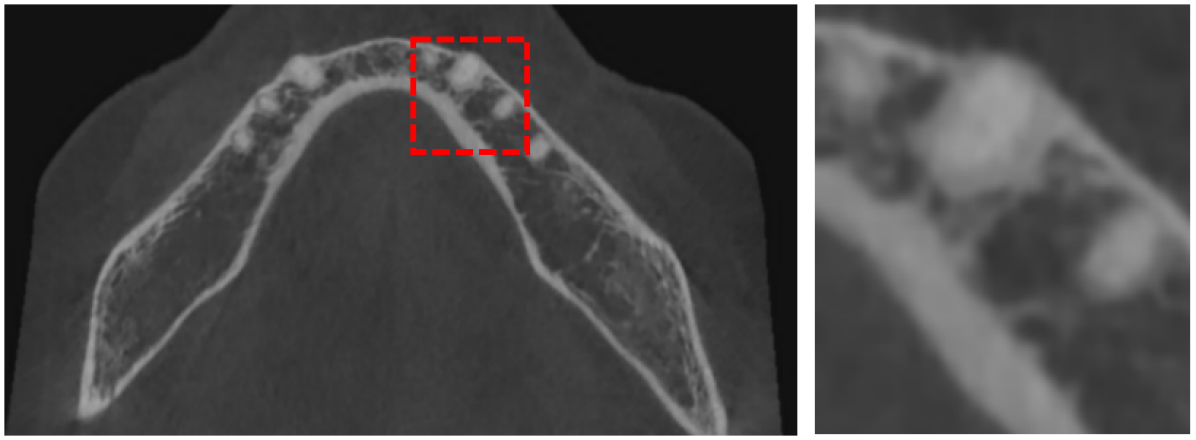

Digitized orthodontic applications in dentistry have increased based on the development of cone beam computed tomography (CBCT) imaging. CBCT is a widely used medical imaging technique that provides high resolution 3D volumetric data. To build an effective computer-aided diagnosis system in orthodontic applications, such as oral treatment planning for tooth reformation and implant guide simulation, automatic segmentation of individual teeth from the CBCT images is an essential prerequisite (Fig. 1). However, accurate segmentation of an individual tooth from a CBCT image is a challenging task owing to heterogeneous intensity distribution, unclear boundaries between the tooth root and alveolar bone (Fig. 2a), and diverse shapes and poses. Moreover, the majority of CBCT images contain severe metal artifacts that hinder the accurate segmentation of teeth (Fig. 2b). In this study, we propose a fully automated instance segmentation framework using 3D images of teeth that is robust to several challenging conditions of the teeth, such as, dynamic poses, missing teeth, inter-tooth proximity, and presence of severe metal artifacts.

Despite all the appealing features from the contour propagating scheme, level-set methods demonstrate a common limitation, i.e., it is difficult to delineate unclear boundaries (Fig. 2). In a CBCT, the boundaries between the tooth root and the alveolar bone have weak edge characteristics (i.e., a low magnitude of gradient; Fig. 2a) and the presence of severe metal artifacts (Fig. 2b), which hinder the accurate propagation of a contour-based level-set method. Furthermore, level-set methods require tedious manual user interaction to define the initial contour [4, 5, 7], indicating a semiautomated algorithm.